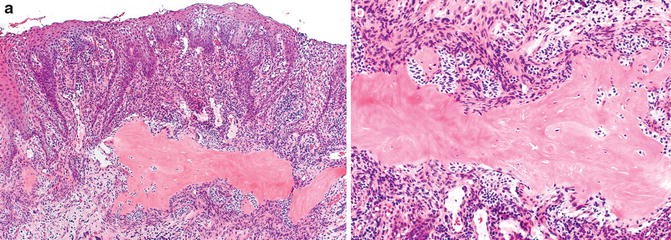

Central Odontogenic Fibroma Histology Collection 2022 Central Odontogenic Fibroma Histology Collection 2022

Central Odontogenic Fibroma Histology